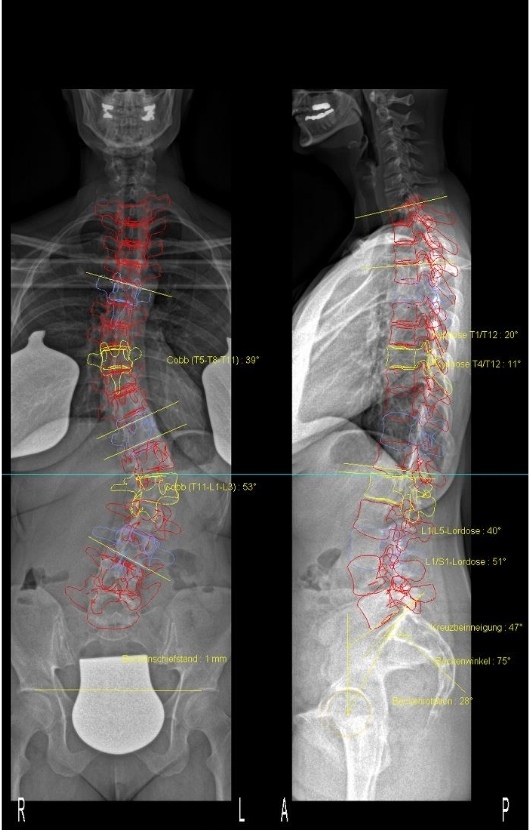

Zu meinem Becken: von Dr. Hoffmann wurden mir nach an die 10 3D-Aufnahmen mit unterschiedlichem Höhenausgleich eine Einlage von 0,9cm verschrieben. Das EOS sieht aber keinen Beckenschiefstand (bzw. nur 1 mm). Also keine Schuherhöhung. Das entspricht nun auch viel mehr meinem eigenen Körpergefühl. Die Einlage hatte ich eigenmächtig nach ein paar Wochen wieder weggelassen.

Der Termin bei Herrn Vogel ging recht schnell. Nach einem kurzen Gespräch wurde ich vermessen und fotografiert. Laut seiner Aussage bekomme ich (wahrscheinlich) ein kurzes Korsett. Ich laufe unter Lumbalskoliose. Die thorakale Krümmung könne man, da kaum Rotation, quasi vernachlässigen.

Diese Aussage konnte ich erstmal gar nicht annehmen, denn seit meiner Skoliose-Karriere auch in beiden Rehas hieß meine Skoliose IMMER thorakolumbal 4bogig und ich musste auch im thorakalen Bereich immer asymmetrisch arbeiten (z.B. Schultergegenzug). Laut Herrn Vogel sei das die ganzen Jahre aber FALSCH gewesen!